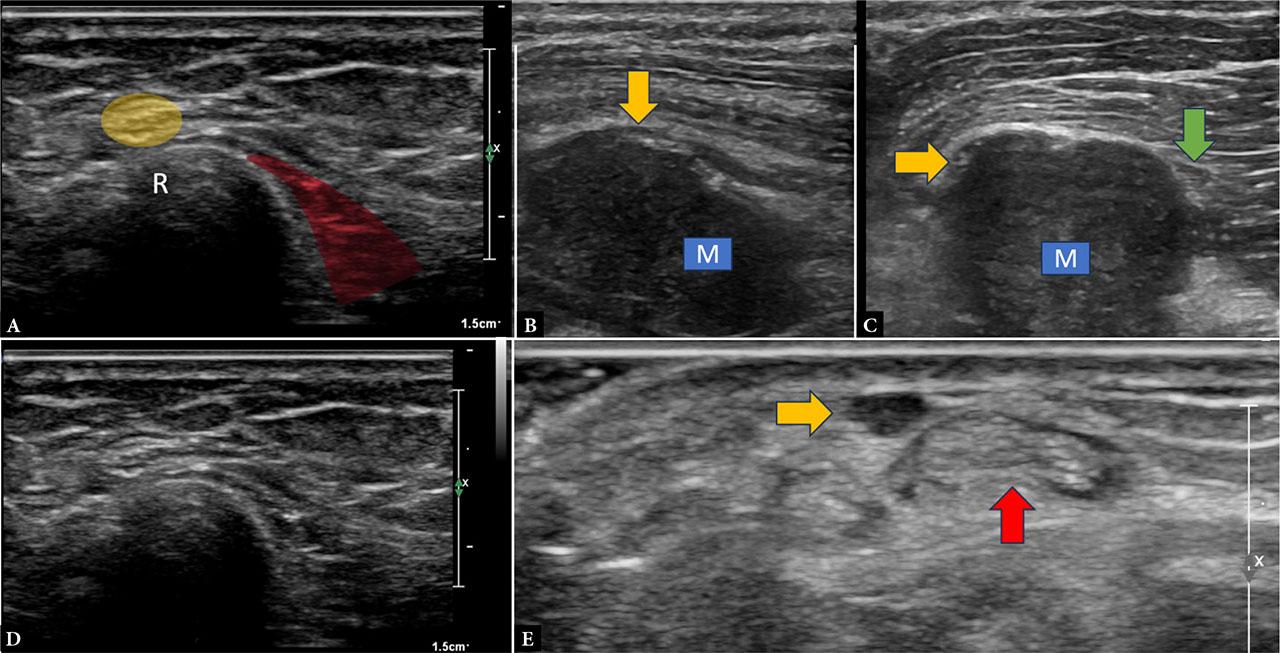

Ultrasound reliably delineates the superficial branch of the radial nerve (SBRN), making it particularly useful in diagnosing Wartenberg’s syndrome – an entrapment neuropathy at the distal forearm and wrist. Anatomically, the SBRN emerges beneath the brachioradialis tendon and lies adjacent to the cephalic vein, both of which serve as important sonographic landmarks. The nerve can be traced from its origin in the proximal forearm as it courses radially and distally, where it can be seen emerging from under the brachioradialis. It then travels in the subcutaneous plane after piercing the muscular fascia and continues distally toward the thumb. At this level, it wraps over the first extensor compartment, a common site of entrapment or iatrogenic injury associated with injections for DeQuervain’s tenosynovitis(11,12) (Fig. 5).

Images A and B demonstrate the normal superficial branch of the radial nerve (yellow) in the distal forearm as it travels in the subcutaneous plane, curving over the distal radius (R) and lying superficial and lateral to the distal brachioradialis muscle (red). Images C and D demonstrate a hypoechoic mass lesion (M) closely abutting the SBRN (yellow arrow) and the posterior interosseous nerve (green arrow) just distal to their origin from the radial nerve in the proximal forearm. Image E demonstrates focal thickening of the SBRN (yellow arrow) at the level of the wrist, superficial to the firstt extensor compartment tendons (red arrow), which show mild effusion consistent with DeQuervain’s tenosynovitis